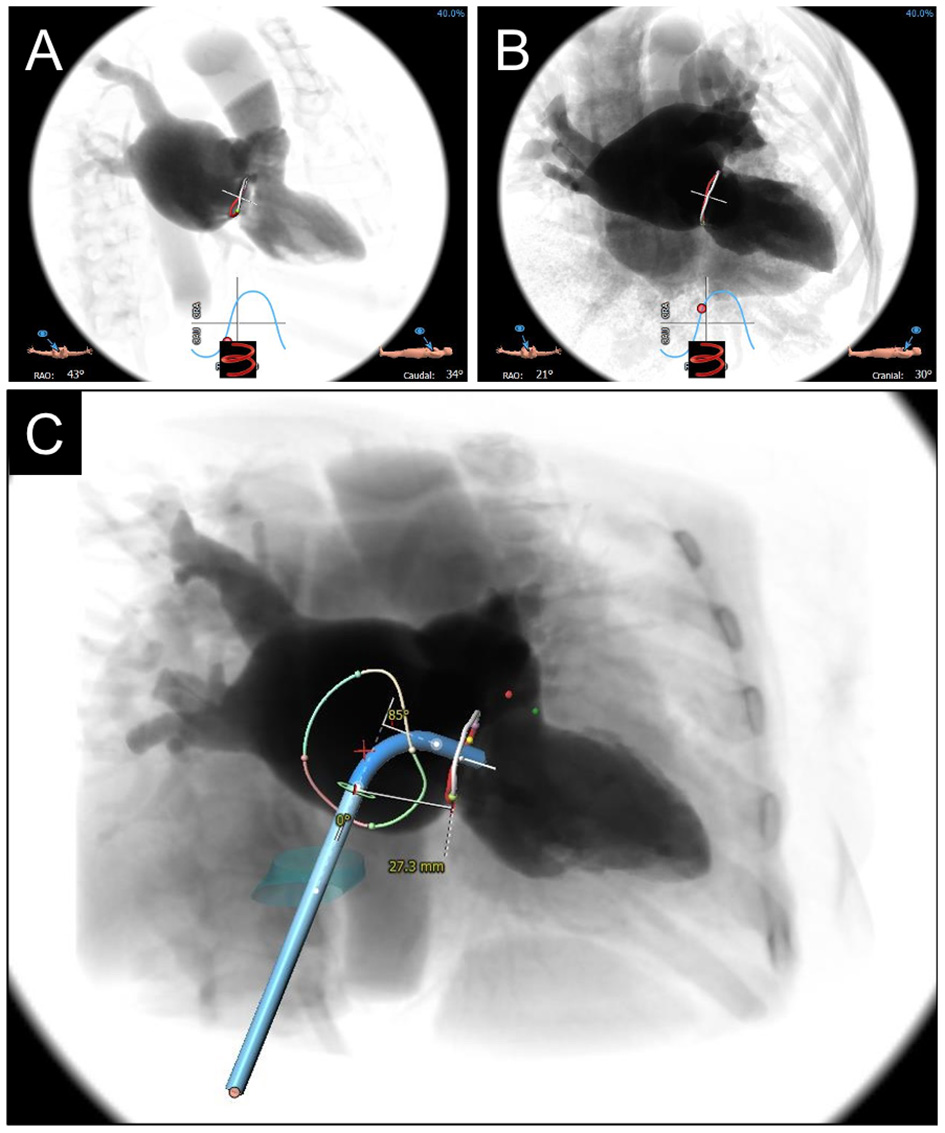

Fluoroscopic angles predicted by CT imaging can streamline TMVR deployment at the time of the procedure (Figure 5). After segmentation of the mitral annulus by CT, coplanar fluoroscopic projections can be formulated along an S-shaped curve with corresponding angles in the left anterior oblique (LAO) or right anterior oblique (RAO) direction and cranial-caudal dimension. Using the fluoroscopic angles along this curve that create coplanar TT (commissural) and SL (3-chamber) views can help in achieving coaxiality at the time of TMVR deployment. Of note, C-arm angulations for the coplanar TT view may not be practical, and a slightly compromised view may be utilized instead. For planning transapical access, the fluoroscopic angle (LAO caudal) for the short axis en face view of the mitral annulus can also be determined by CCTA.

Figure 5

CCTA-based Fluoroscopic Simulation for TMVR access planning. Projected Fluoroscopic coplanar angles can be found along the displayed S-curve. A coplanar working view (A) and modified 4-chamber view (B) are displayed for a planned valve-in-ring procedure. (C) Full transseptal access planning is shown, with a projected catheter path through the IVC (turquoise cylinder) and across the interatrial septum for coaxial valve implantation from the working view. Catheter bend angle is displayed (85 degrees) and ideal entry distance from the mitral annulus (27.3 mm).